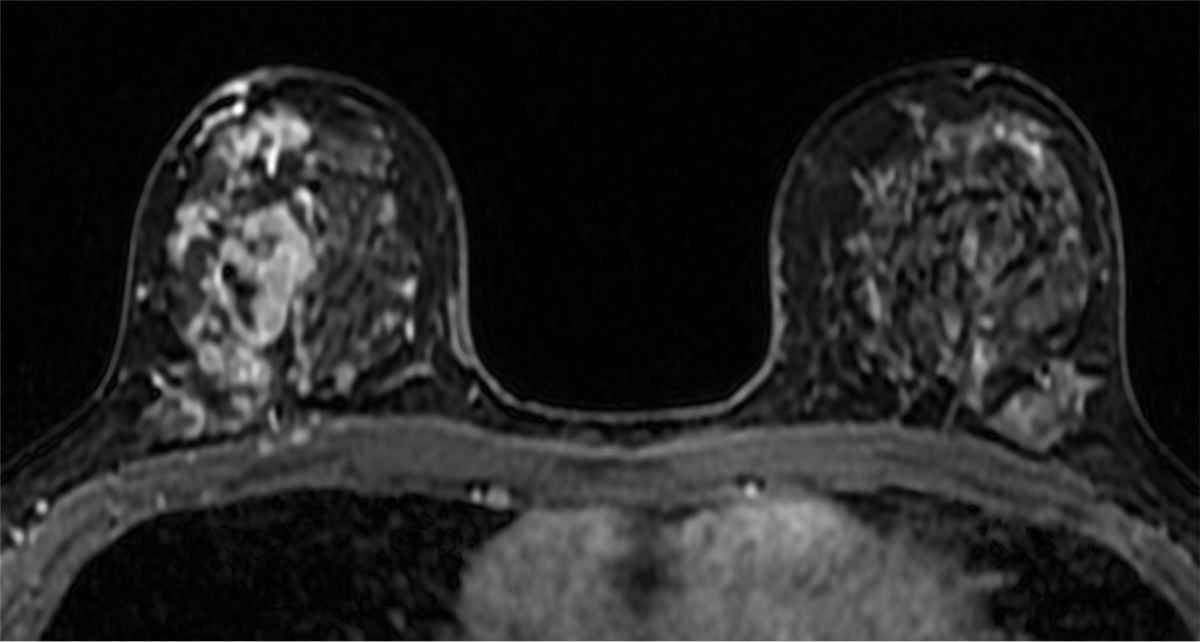

針生検の結果、ductal carcinoma in situ (DCIS)が疑われた。手術加療の方針となり、術前の広がり評価目的に造影MRIを撮像した。乳房全切除術及びセンチネルリンパ節生検を施行し、最終病理診断はDCISであった。

当該疾患の診断における造影MRIの役割

乳腺MRIは乳癌の広がりを高精度に診断できる。この症例においてもマンモグラフィーでは病変を指摘出来なかったが、MRIでは病変が明瞭に描出され、エコーで捉えられる領域よりも広範に及んでいる事が示された。3D解析を用いることでより俯瞰的な評価ができ、術式の選択や切除範囲の一助となった。

近年では、圧迫センシングなどの撮像技術の進歩によりUF-DCE MRIが可能となった。造影直後の超早期からの数秒毎の撮像を行うことで、乳腺組織とのコントラストを高め、血流豊富な腫瘍と腫瘍関連血管の評価に優れている。使用する造影剤量の増加や撮像時間の延長なく、良悪性の鑑別や薬物療法の治療効果予測に役立つと報告されており、更なる臨床応用が期待されている。